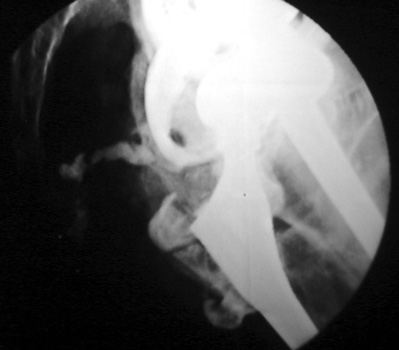

Dry tap secondary to sinus tract decompression

Sinus tract draining posteriorly